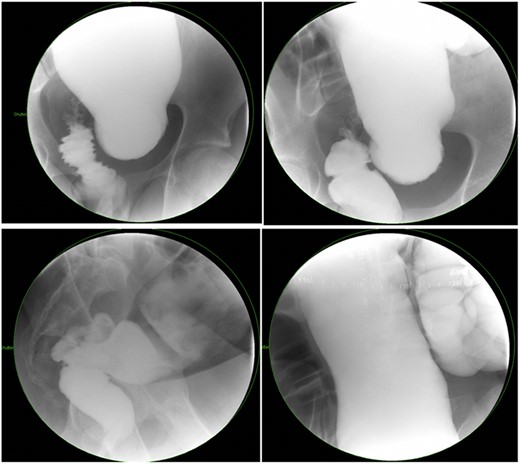

There is a subset of patients in whom primary transanal pull-through in those >2 years of age at the time of surgery is possible. While a previous case series reported that 18.8% of their late-diagnosed HD patients underwent transanal primary pull-through, these authors did not describe outcomes or reasons for choosing the operative approach [7]. In case series, the characteristics of patients who were able to undergo primary transanal-only pull-through include overall earlier age (2–6 years) vs. those diagnosed later. On contrast enema, they exhibited a limited degree of megacolon (Figs 1 and 2). Proximal colonic dilation was absent in all four patients that we felt were good candidates for a transanal-only approach. However, proximal colonic dilation (proximal of the sigmoid) was visualized in 15 patients, and therefore, a transanal-only approach was not offered. The ability to identify a clear transition zone low in the rectosigmoid was also observed in each patient. Finally, the ability to empty the colon preoperatively whether through laxatives or rectal irrigations was also present.

Representative contrast enema study of an older child with a large amount of proximal colonic dilation of the sigmoid and descending colon, seen here across multiple views during contrast enema (Not a candidate for transanal only).